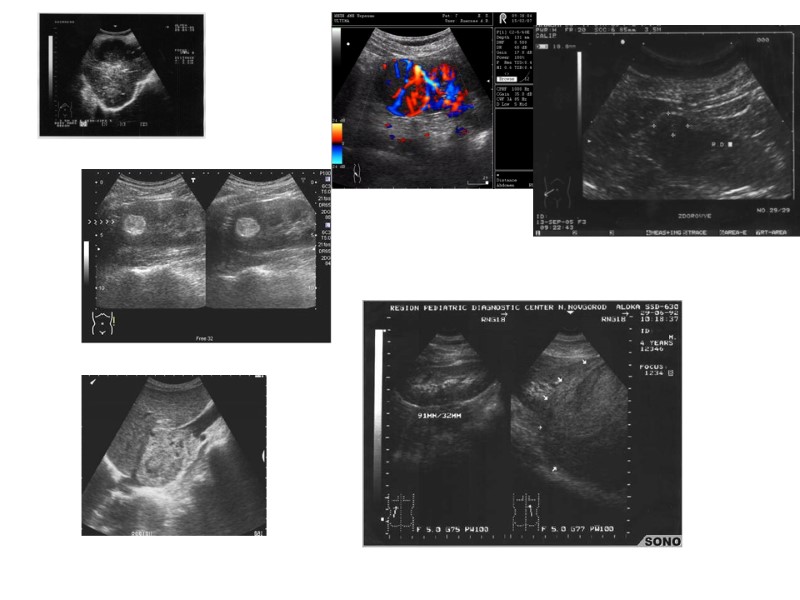

Почечно-клеточный рак

Диагностика УЗИ

Диагностика опухолей почек УЗИ РАДИОИЗОТОПНЫЕ МЕТОДЫ РЕНТГЕНОЛОГИЧЕСКОЕ ИССЛЕДОВАНИЕ

Диагностика Основывается на данных клинического, ультразвукового исследований, компьютерной и магнитно-резонансной томографии, лабораторной диагностики.

При исследовании мочи нередко выявляют эритроцитурию, протеинурию, лейкоцитурию. Общий анализ крови – повышение СОЭ, снижение гемоглобина, содержания моноцитов, эозинофилов, нейтрофилов, лимфоцитов. УЗИ – удаётся определить размеры почки, неоднородную плотность паренхимы, деформацию чашечно-лоханочной системы, локализацию узла.